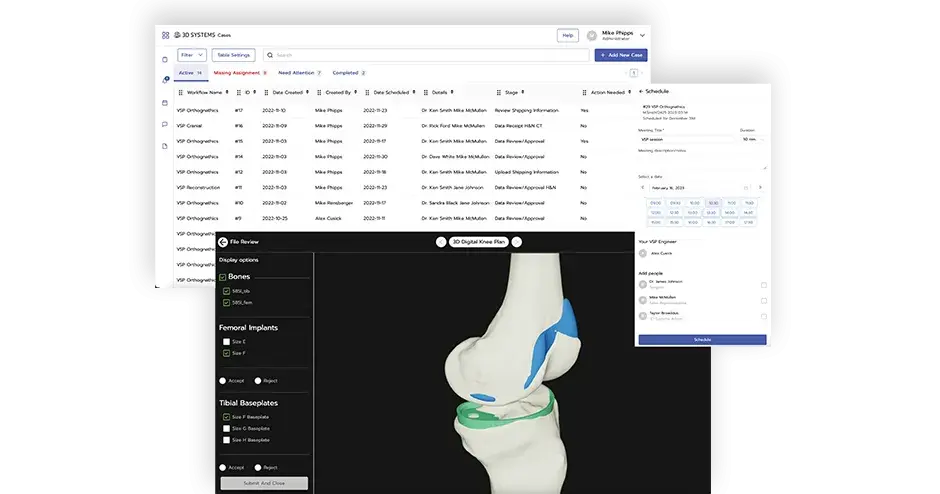

3D Systems partners with device manufacturers and healthcare providers to transform surgical outcomes for both patients and surgeons. We create custom solutions that help translate virtual surgery into the OR with the goal of improving outcomes and the overall patient experience. Our multifaceted offerings include advanced design and planning software, expert planning services and a full range of custom implants and instrumentation.